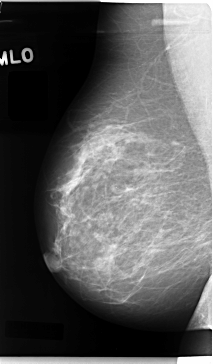

C_0059_1.LEFT_MLO

LEFT_MLO LINES 4712 PIXELS_PER_LINE 2712 BITS_PER_PIXEL 12 RESOLUTION 50 OVERLAY